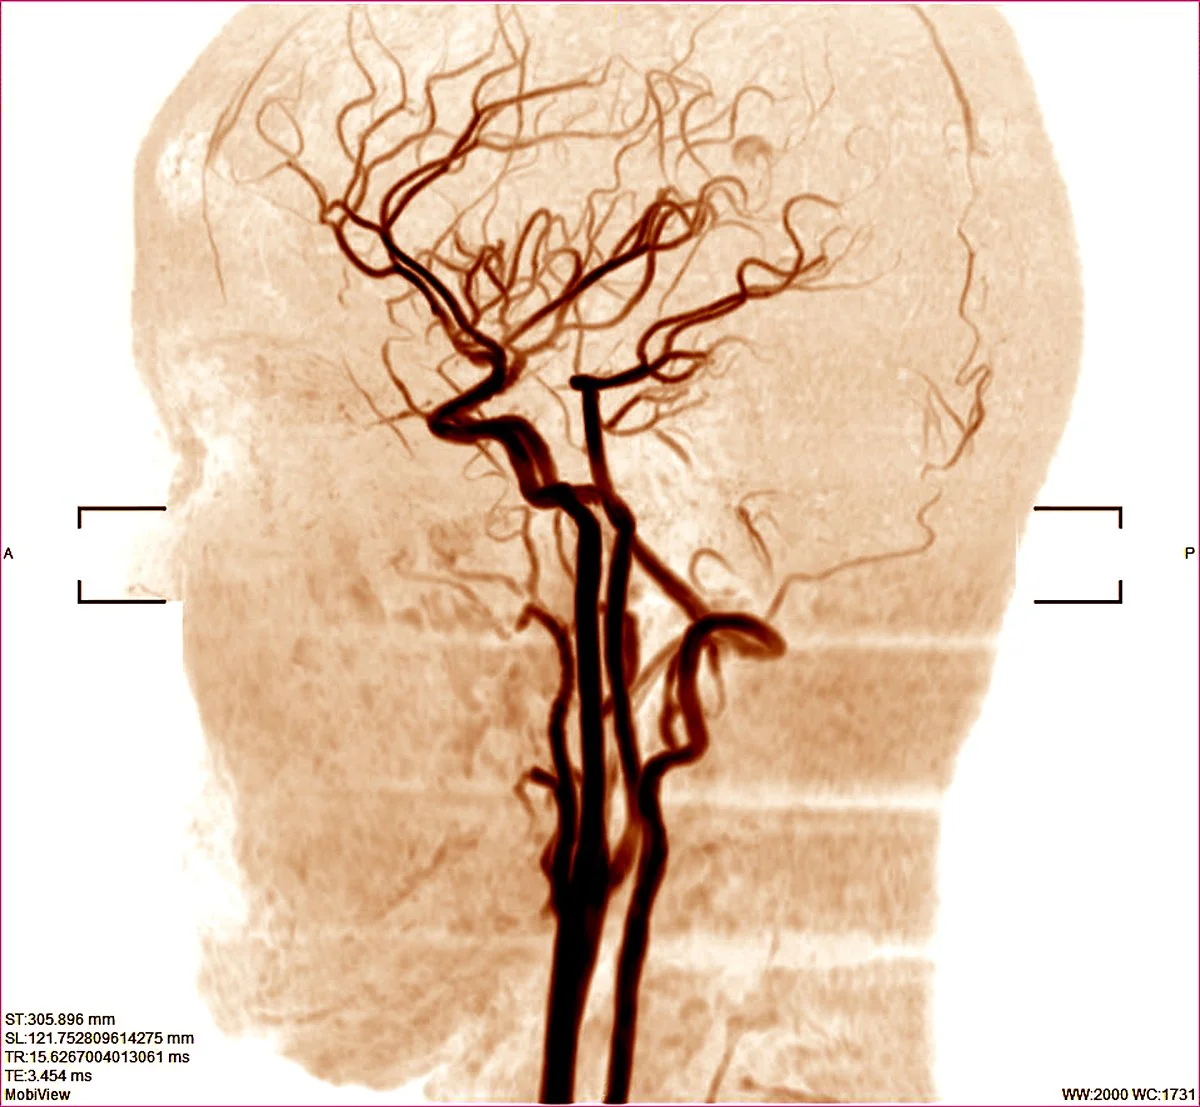

보통 혈관CT 또는 혈관 MR을 시행한 후 혈관의 병변이 의심되는 경우에 정밀한 진단을 위해서 혈관조영술을 시행하게 됩니다.

Q. 혈관조형술이란 무엇인가요?

'혈관조형술'이란 뇌혈류의 역동학적 흐름을 정확하게 확인하기 위해 시행합니다. 대퇴부위에 있는 대퇴동맥을 이용하여 혈관조영술을 시행합니다. 속이 비어있는 관(카테터)을 철사를 따라서 뇌혈관 입구에 위치시킨 뒤 철사를 빼내고 카테터를 통해 요오드를 포함하고 있는 수용성 물질인 조영제를 주입하게 되면 동맥 자체 및 동맥으로부터 혈액을 공급받는 정상 구조 및 병변까지 관찰할 수 있습니다.